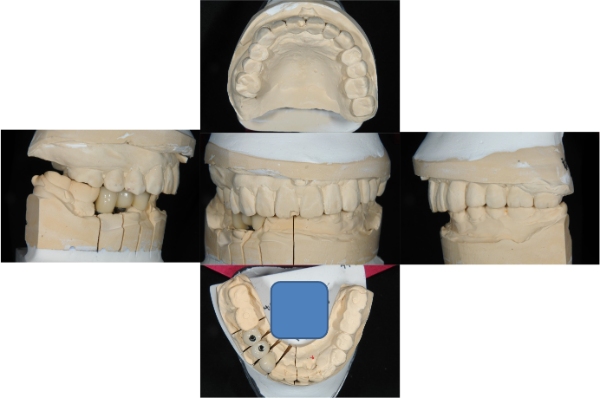

上面弓與咬合器

咬合器上製作假牙

治療後口內照